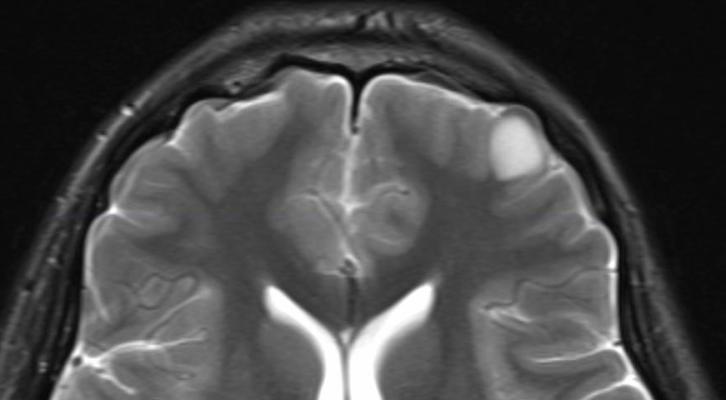

Brain tumors can affect brain function if they grow large enough to press on surrounding nerves, blood vessels and tissue. There is homogeneous enhancement with a broad dural tail. We see that in the first image, to the left side of the brain, there is a tumor formation, whereas in the second image finally, we come to the stage where we will fit the image data to the trained neural network.

Brain tumor symptoms include headaches, nausea or vomiting surgery is the usual first treatment for most brain tumors. Primary brain tumors include tumors that originate from the tissues of the brain or the brain's immediate surroundings. Mri (magnetic resonance imaging) with gadolinium: Show brain tumor at right parietal lobe of cerebrum.